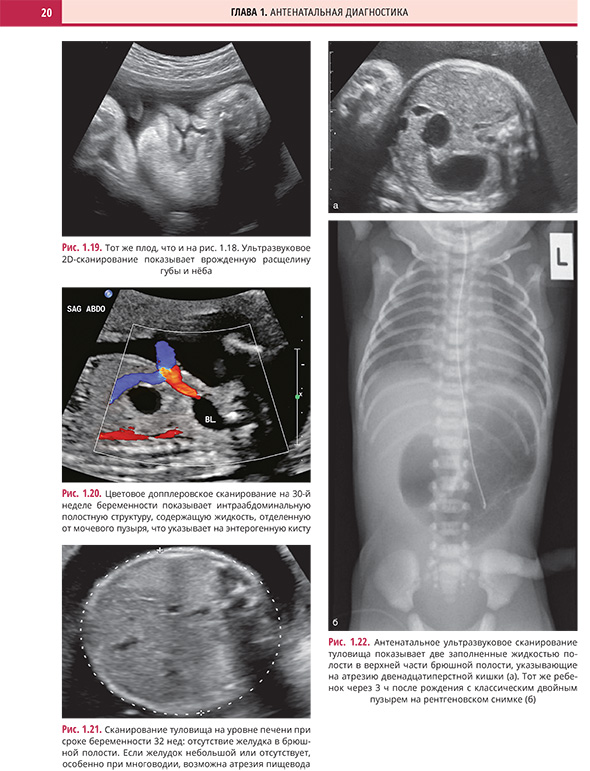

Дефекты передней брюшной стенки